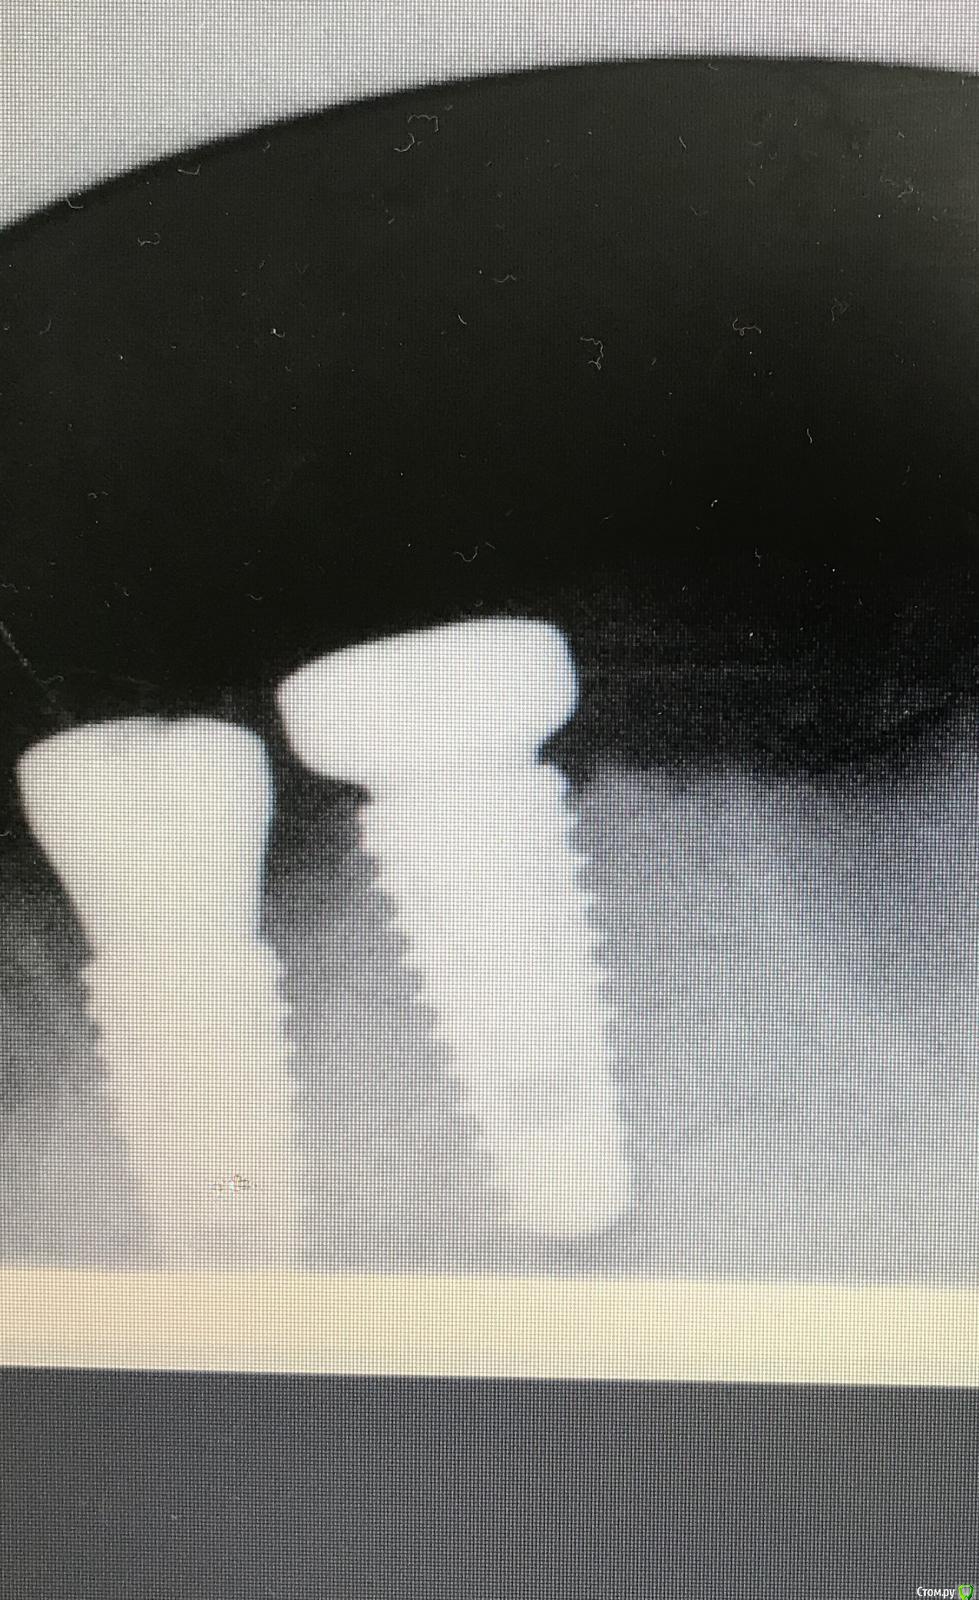

dr.Dre Опубликовано 18 мая, 2019 Поделиться Опубликовано 18 мая, 2019 Добрый вечер .Коллеги что делать в такой ситуации,кость d1 ,ели разработал ложе под имплантанты .Хотел установить субкрестально ,не смог кость очень тугая ,фрезой кортикальной проходил ничего не поменяло.Два витка торчат над костью , усилие 45 Ньютон .Могу ли через неделю после снятие швов,попробовать дотопить их?Имплантанты megagen Anyone 4/8,54,5/8,5 Ссылка на комментарий

kramer Опубликовано 19 мая, 2019 Поделиться Опубликовано 19 мая, 2019 А есть снимок? Если не помогает кортикальная фреза, я беру сверло следующего диаметра. 2 Ссылка на комментарий